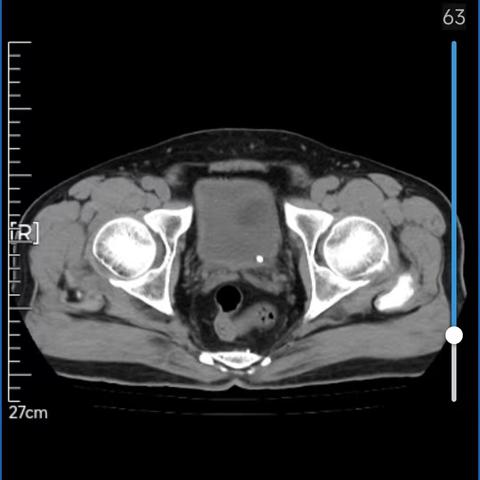

太原西山医院泌尿外科 再次成功实施输尿管软镜下钬激光碎石术